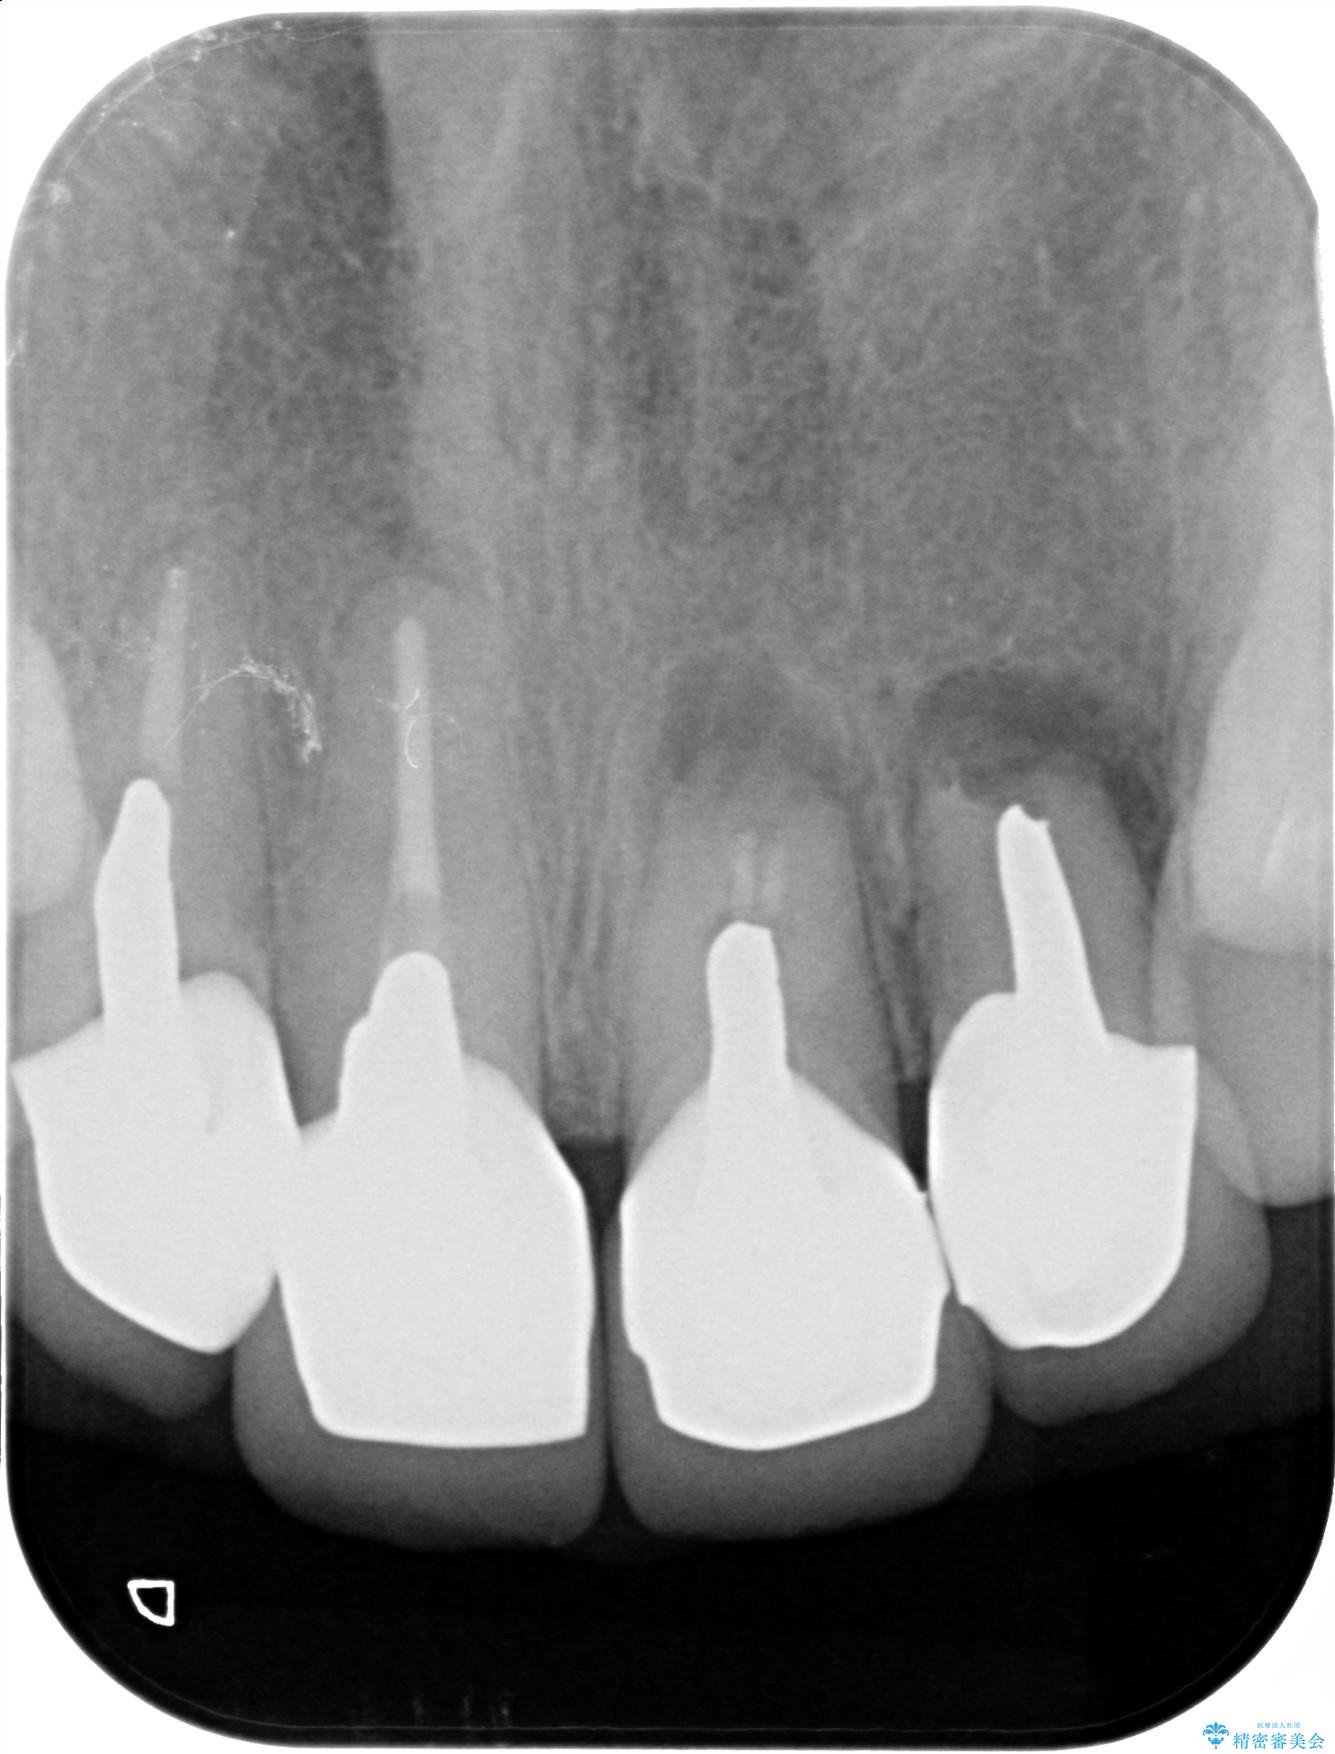

一見して問題ないように見える左側の2前歯は、セラミックを除去してみると亀裂や虫歯の再発が見られました。

抜歯時に可及的に歯肉のボリュームを保つよう骨充填材とコラーゲン製剤による填塞を行い審美的かつ機能的なブリッジとなるよう治療を進めます。

治療前

歯槽堤保存術を併用したブリッジ治療 治療前画像 歯槽堤保存術を併用したブリッジ治療 治療前画像 歯槽堤保存術を併用したブリッジ治療 治療前画像 歯槽堤保存術を併用したブリッジ治療 治療前画像 歯槽堤保存術を併用したブリッジ治療 治療前画像 歯槽堤保存術を併用したブリッジ治療 治療前画像 歯槽堤保存術を併用したブリッジ治療 治療前画像 歯槽堤保存術を併用したブリッジ治療 治療前画像 歯槽堤保存術を併用したブリッジ治療 治療前画像 歯槽堤保存術を併用したブリッジ治療 治療前画像